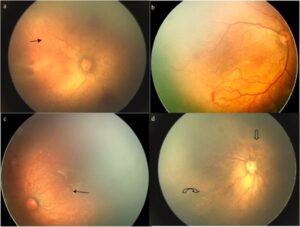

- Indirect Ophthalmoscopy: The specialist uses a light source and a special lens to visualize the retina. This method allows for a detailed view of the retinal blood vessels and the overall condition of the retina.

- Retinal Imaging: In some cases, advanced imaging techniques like fundus photography or optical coherence tomography (OCT) may be used to assess the retina more thoroughly.

- Staging and Classification:

- The ophthalmologist evaluates the retina for signs of ROP and assigns a stage from 1 to 5 based on severity:

- Stage 1: Mild, with abnormal blood vessel growth.

- Stage 2: Moderate, with more pronounced changes.

- Stage 3: Severe, with more abnormal growth and potential complications.

- Stage 4: Partial retinal detachment.

- Stage 5: Total retinal detachment.